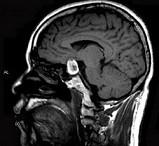

问题 男性,55岁,头痛一年余,两个小时前突然出现剧烈头痛,MRI检查如图所示,最可能的诊断为 ( )

选项 A、垂体瘤并卒中 B、动脉瘤 C、脑膜瘤 D、颅咽管瘤 E、垂体瘤

答案 A